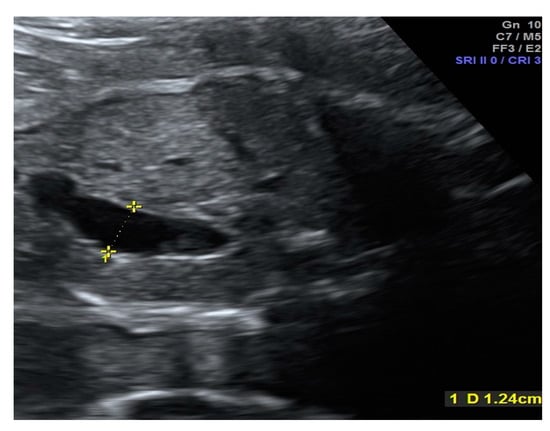

Prenatal Prediction of Outcome by Fetal Gastroschisis in a Tertiary Referral Center

2. Materials and Methods